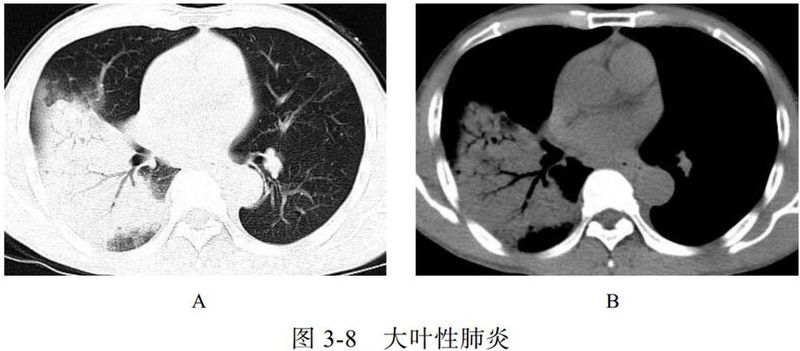

(一)大叶性肺炎

大叶性肺炎以秋冬季节多见,常见于青壮年,致病菌主要为肺炎链球菌、肺炎克雷伯菌、军团菌,常累及整个肺叶或肺段。临床表现为突然发病、畏寒发热、胸痛、咳嗽、咳痰,白细胞和中性粒细胞计数明显升高等。

影像学表现:

(1)充血期肺组织呈边缘不清的云雾状影,实变期呈大片实变影(图 3-8A)、充气支气管征(图 3-8B),消散期呈散在斑片状影。

(2)肺炎链球菌肺炎与肺炎克雷伯菌肺炎的区别:前者支气管充气征清晰可见,可达胸膜下;后者因分泌物黏稠,支气管充气征显示不佳。

(3)溶血链球菌肺炎容易出现空洞。

图片